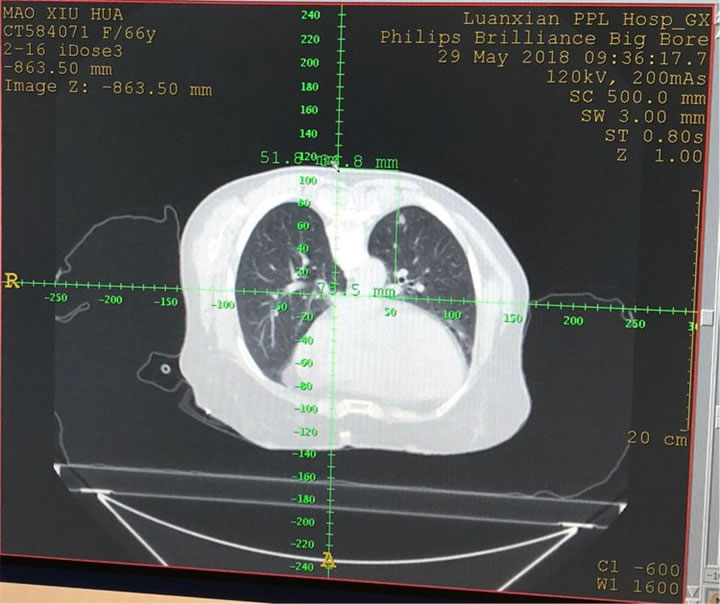

患者女性66歲,右上肺癌,5個(gè)月前手術(shù)切除。體檢發(fā)現(xiàn)左下肺結(jié)節(jié),經(jīng)MDT考慮惡性程度高,決定消融治療并行同步活檢。于2018年5月29日10:00開始手術(shù)。手術(shù)由陳寶明教授指導(dǎo),由王冠,張玉衛(wèi)醫(yī)師完成。這是陳寶明教授團(tuán)隊(duì)又一力做,添補(bǔ)了這一技術(shù)領(lǐng)域的空白。

小結(jié)節(jié)狀態(tài)及位置,設(shè)計(jì)穿刺路徑